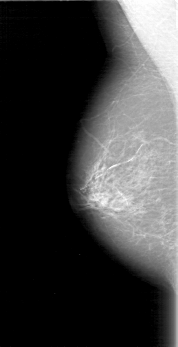

D_4097_1.LEFT_CC

LEFT_CC LINES 4726 PIXELS_PER_LINE 2176 BITS_PER_PIXEL 12 RESOLUTION 43.5 OVERLAY

FILE: D_4097_1.LEFT_CC.OVERLAY

TOTAL_ABNORMALITIES 1

ABNORMALITY 1

LESION_TYPE MASS SHAPE IRREGULAR MARGINS ILL_DEFINED

ASSESSMENT 2

SUBTLETY 3

PATHOLOGY BENIGN

TOTAL_OUTLINES 1

BOUNDARY